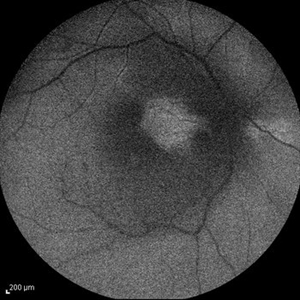

Behcet's Disease Behcet's DiseaseMar 13 2013 by Hamid Ahmadieh, MD Early phase FA of the left eye of a 23-year-old man with retinal vasculitis due to Behcet's disease . Photographer: Solmaz Shahmohammad, Negah Eye Center, Tehran Imaging device: Heidelberg Spectralis Condition/keywords: retinal vasculitis